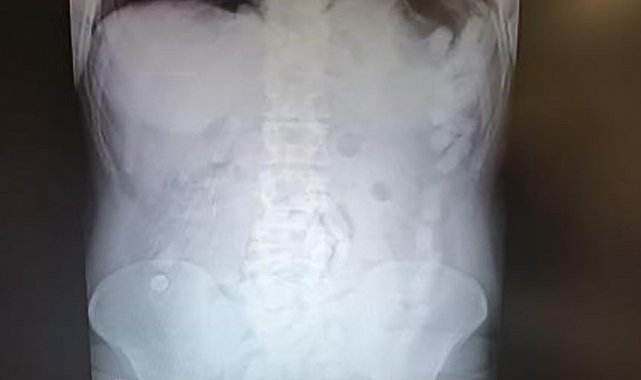

4 Mayıs 2024'te Kayseri İl Emniyet Müdürlüğü Narkotik Suçlarla Mücadele Şube Müdürlüğü ekipleri, yabancı uyruklu A.H.'nin ülkeye giriş yaparak üzerindeki uyuşturucu maddeleri Kayseri'ye getireceğini tespit etti. Şahsı takibe alan ekipler, yerini tespit ettikten sonra operasyon düzenledi. Kayseri Şehir Hastanesinde ultrason çekimi ile yapılan kontrolde şahsın midesinde çok sayıda kapsül olduğu tespit edildi. Yapılan operasyonla şahsın midesinden çıkarılan 100 adet kapsülün içerisinde 729 gram uyuşturucu madde ele geçirildi. İşlemlerinin ardından adliyeye sevk edilen şüpheli, çıkarıldığı mahkemece tutuklanarak cezaevine gönderildi.